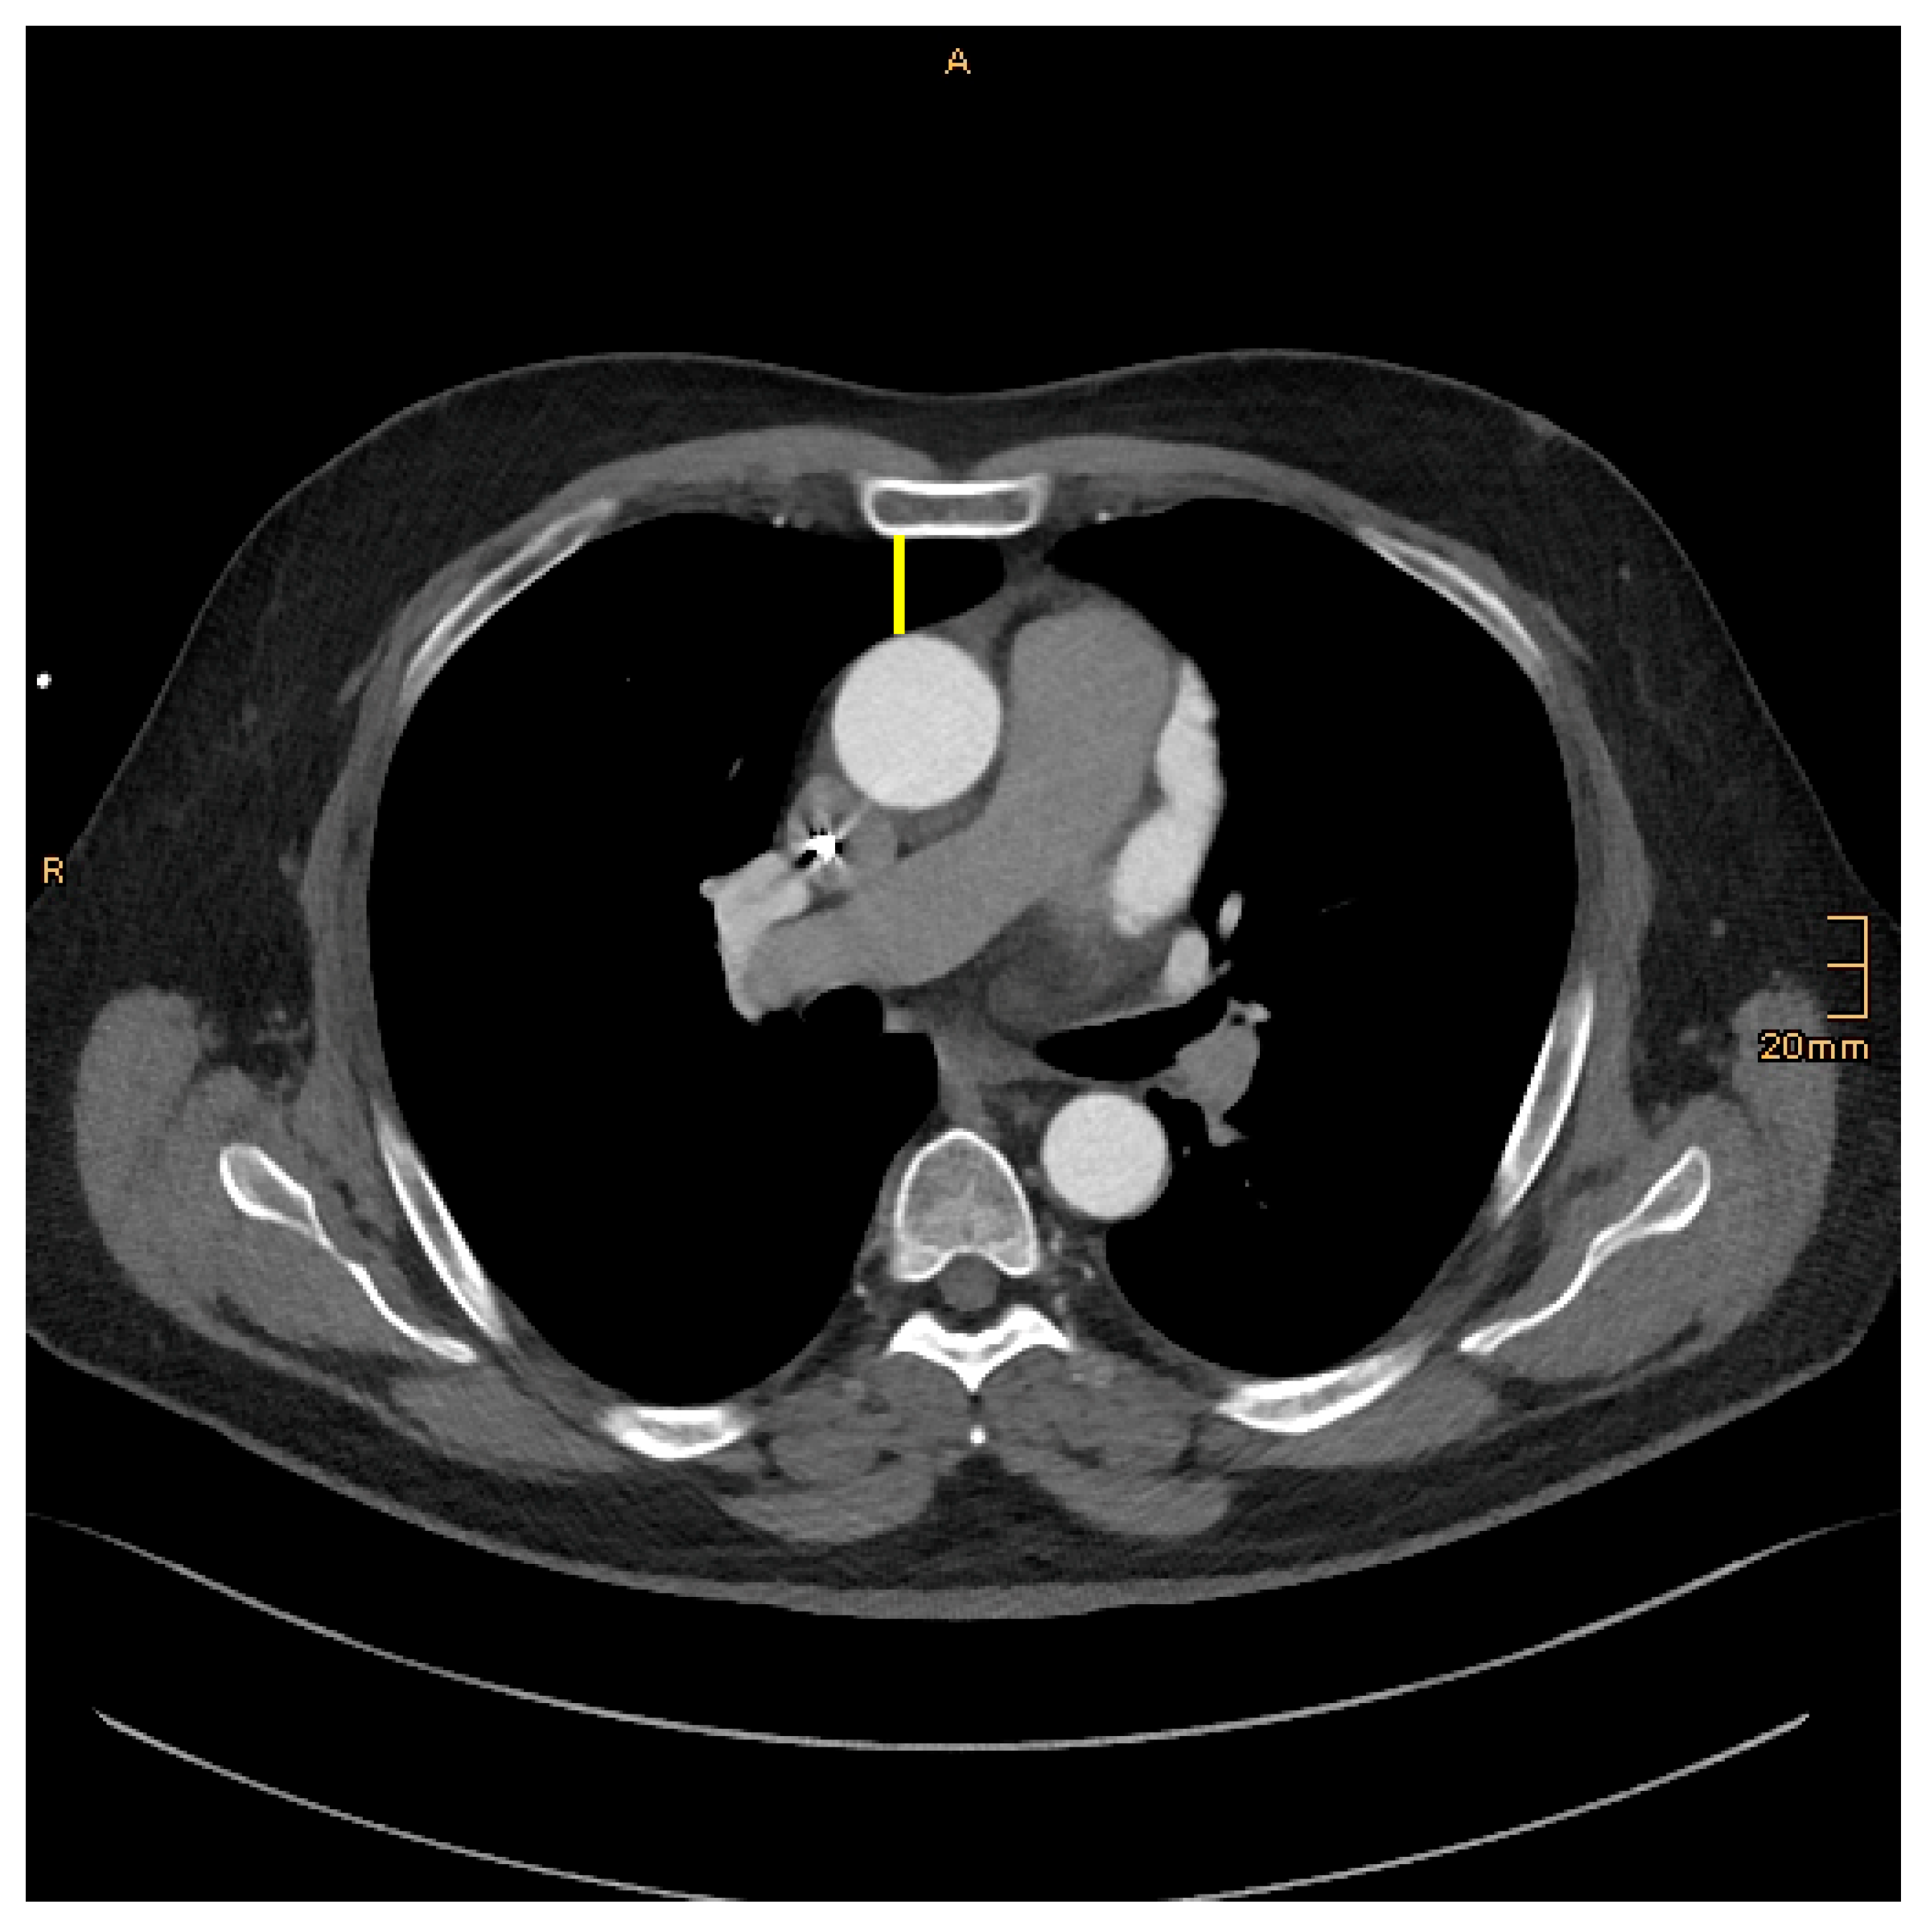

ICS–Width of the intercostal space:

In multiplanar reformatting (MPR), the width of the corresponding intercostal space just below the nipple reflecting the entry site was measured.

Figure 3. ICS–Width of the intercostal space: yellow. The red, green, and blue lines represent the orthogonal planes generated by the Multi-Planar Re-construction (MPR) plugin, facilitating three-dimensional assessment of the CT dataset.